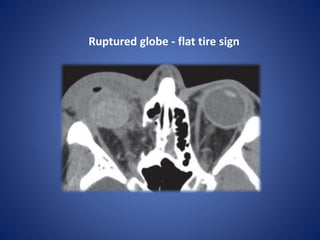

Ruptured globe - flat tire sign

Ruptured globe -flat tire sign